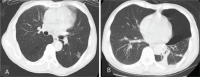

Case summary: A 68-year-old man presented with 2 months of progressive lower back pain. Visualization with magnetic resonance imaging (MRI) revealed multiple collapsed vertebrae from T12 to S3, as well as an altered signal intensity at the T3 vertebra. The patient was diagnosed with MM upon examination. A chest computed tomography (CT) scan revealed a round mass in the left lower lobe of the lungs, and a CT-guided needle biopsy uncovered a moderately differentiated adenocarcinoma. There were no additional notable findings in the left lung using positron emission tomography computed tomography (PET-CT). Therefore, a diagnosis of MM with pulmonary adenocarcinoma was made. Surgery was performed to excise the lung cancer. Bortezomib was used as first-line induction therapy against both tumors and lenalidomide was used for maintenance. The patient went into complete remission. Using this combined chemotherapy, the patient has survived for over 3 years since a diagnosis was made despite relapsing twice after the first year.